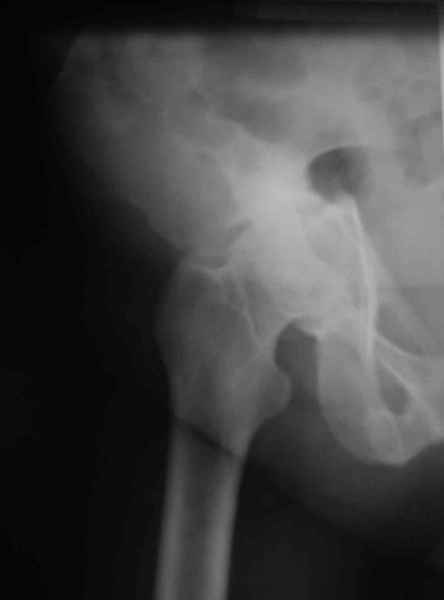

Ув.коллеги,нужен совет по представленному случаю. Пациентка, 50лет. В 2003 году в результате дтп получила перелом вертлужной впадины. 1.5 месяца находилась на скелетном вытяжении, в дальнейшем до 10 месяцев после травмы ходила без опоры на конечность. Вернулась к труду, но в 2006 году перешла на инвалидность и была поставлена в областную очередь эндопротезирования. В данный момент уже находится в отделении, но, судя по рентгенограммам и данным КТ, сращения на уровне перелома не произошло. Что предпочесть? 1.Остеосинтез с костной пластикой и последующим эндопротезированием. 2."Октопус". 3.Кольцо Мюллера. Заранее благодарен за ответы и ценные замечания.

при более внимательном анализе КТ, передняя колонна выглядит сросшейся, остается синтезировать заднюю?Похоже был низкий двухколонный перелом или перелом передней с задним полупоперечником?